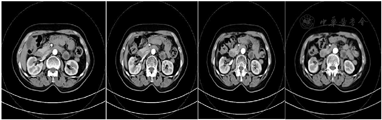

病例2专科检查:双肾区无隆起,双肾及输尿管移行区无叩压痛,膀胱区不充盈,无压痛。2021年5月11日多排CT肾肿瘤CTA(优维显)。CT所见:右肾下极内部见一约3.4 cm×3.0 cm×3.0 cm大小的异常强化灶,病灶边界尚清晰,局部膨出于肾脏表面,边缘见钙化灶,动脉期明显不均匀强化,CT值约160 HU,静脉期CT值约137 HU。腹主动脉前壁分出一支副肾动脉(A)走行至右肾下极前部,远段供应肿瘤。右主肾动脉远段近肾门处分成前、后两分支:前支:先分出一细小分支,供应右肾上极内侧,后分为上、下两分支:前-上支:供应右肾上极前部。前-下分支:供应右肾上极中部。后支:分为上、下两支。后-上支:供应右肾中上极后部。后-下支:供应右肾下极后部。印象及建议:右肾下极内侧部占位,考虑肾细胞癌(透明细胞癌),右侧副肾动脉供应肿瘤(图6)。

病例2:2021年8月23日泌尿外科门诊多排CT胸部平扫,CT所见:右肾部分切除术后,术区见金属影及片状低强化影。左肾形态未见异常,肾实质内未见明显异常密度影。双侧肾上腺形态、密度未见异常。印象及建议:右肾部分切除术后,术区片状低强化灶,考虑术后改变可能,建议随诊复查(图11)。

2021年12月7日泌尿外科门诊多排CT中腹部直接增强(欧乃派克),CT所见:右肾部分切除术后,术区片状低强化灶,较前2021年8月23日范围稍缩小,考虑术后改变可能,建议随诊复查。